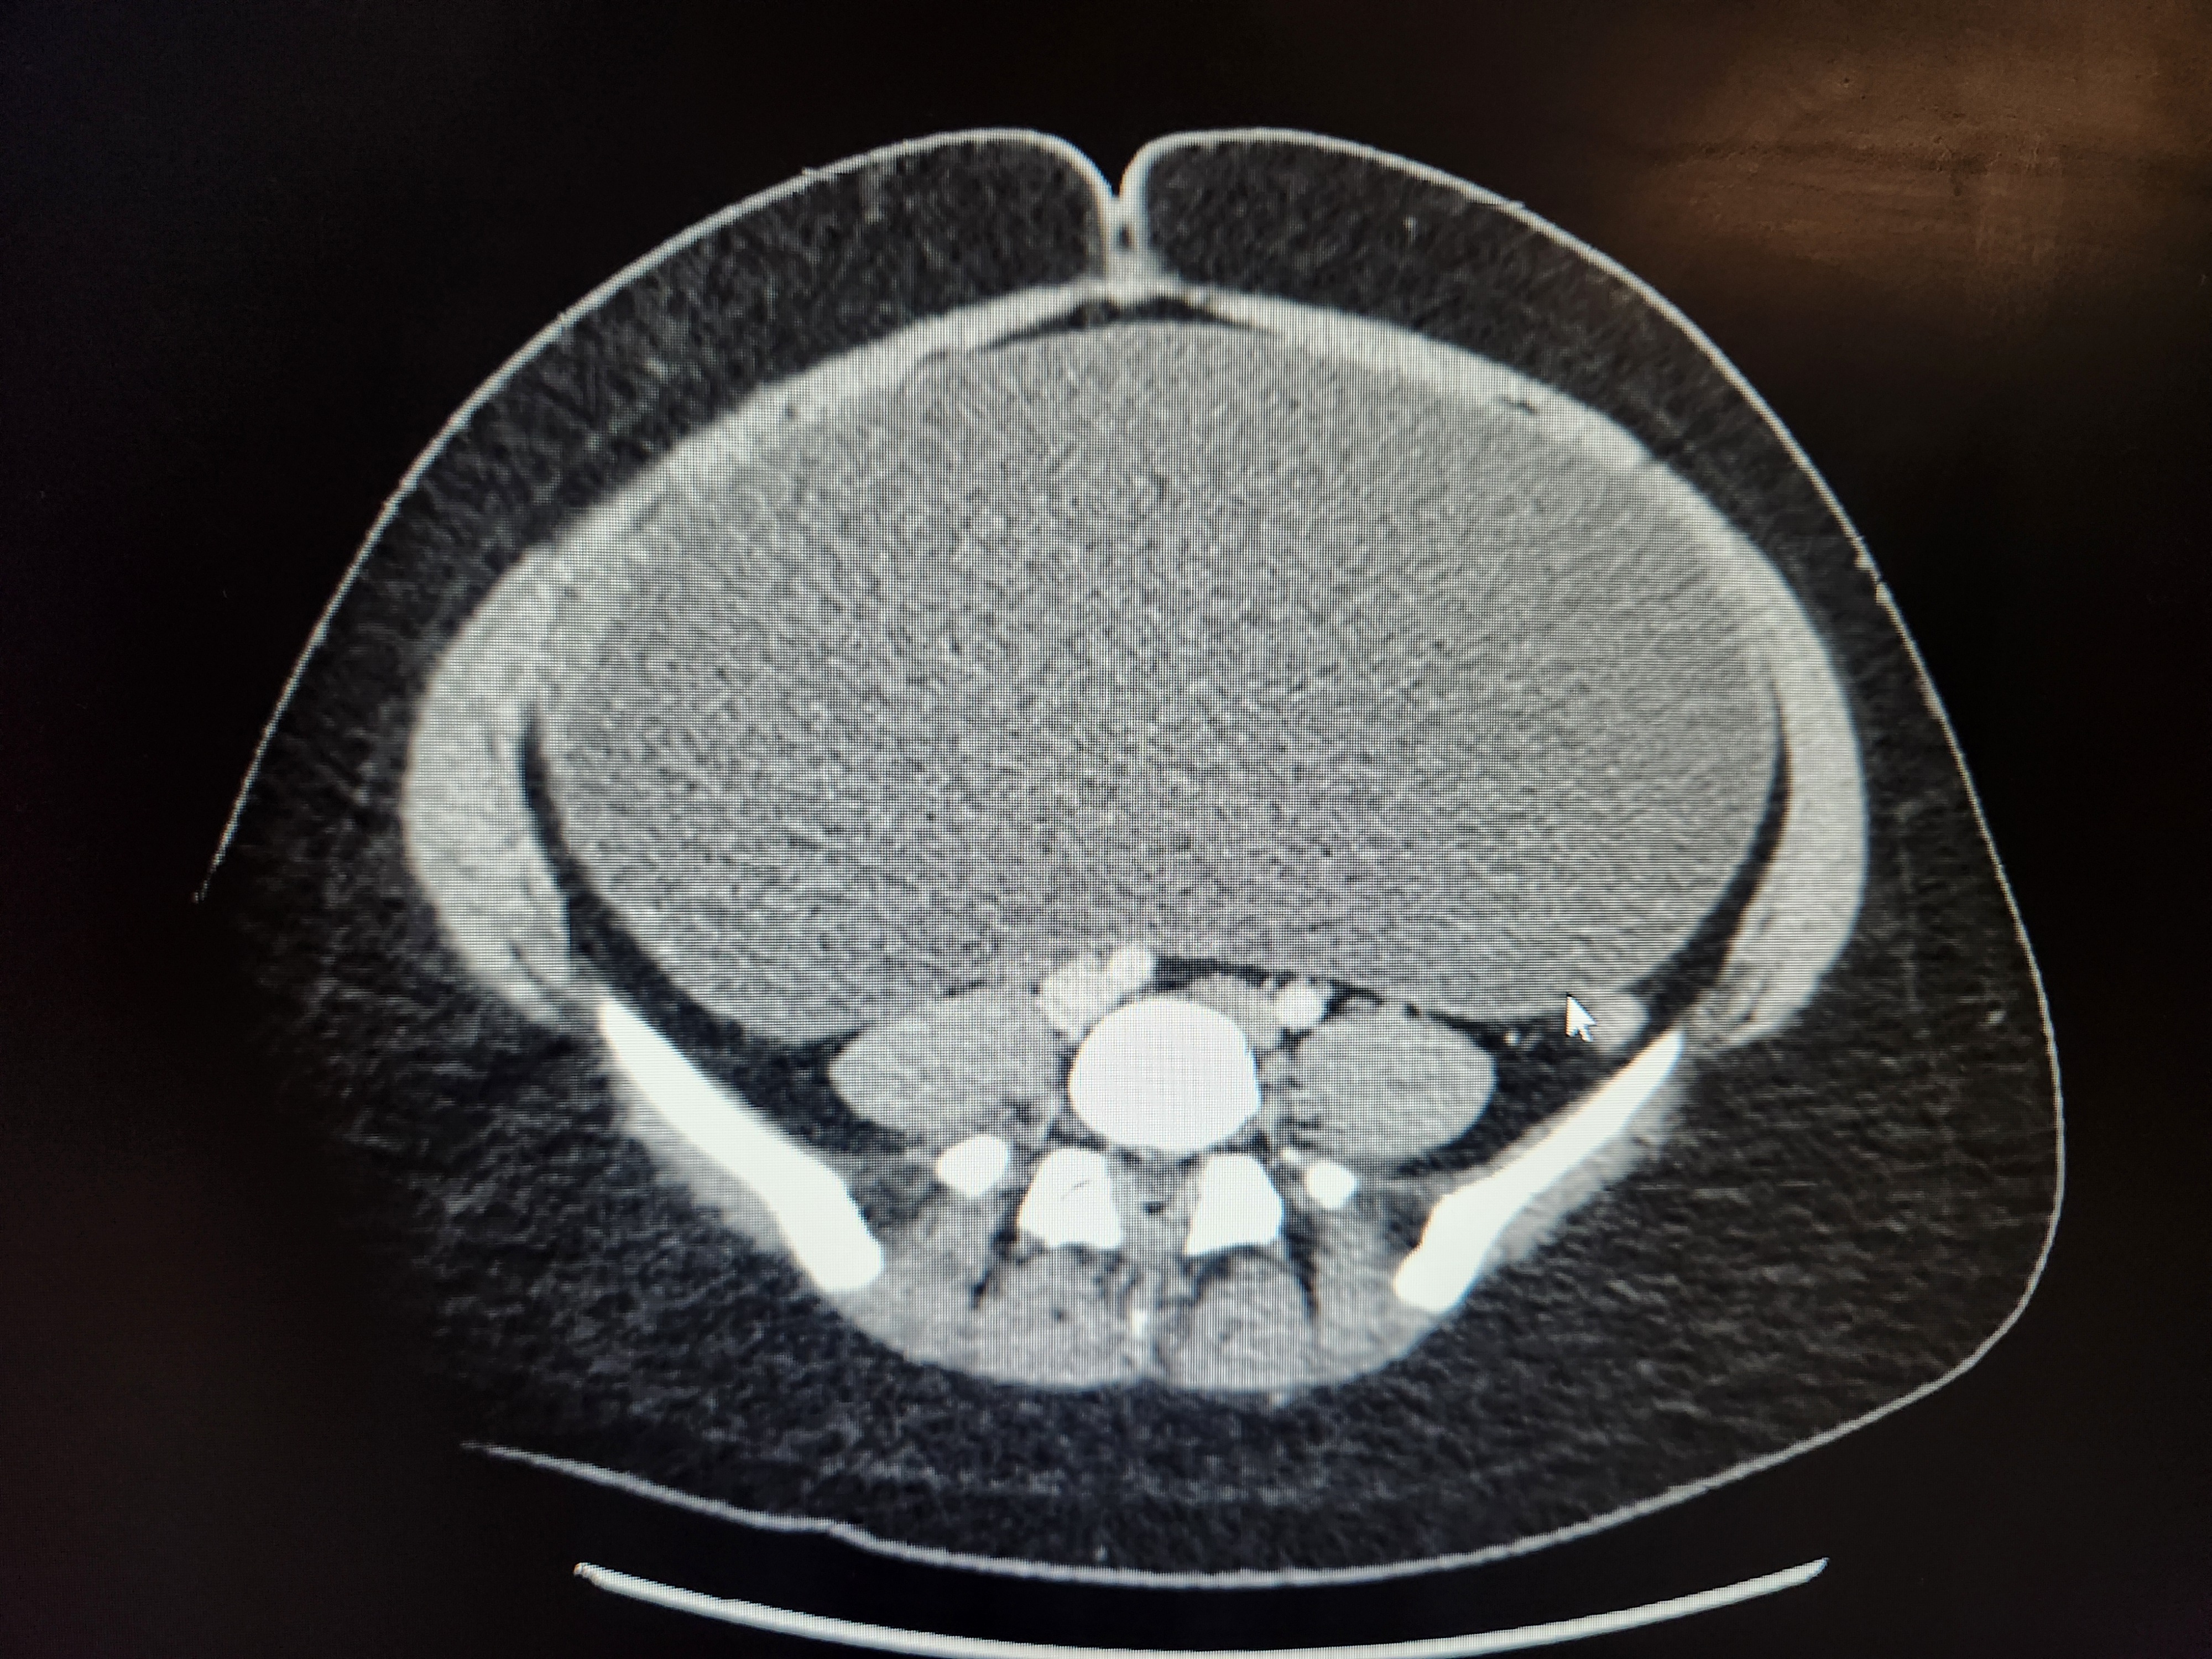

MANY hours in the local ER, labs, more labs, 3x ultrasounds, CT, pelvic & abdominal MRIs, consults with GYN, GYN/OC, hospitalists, GI, & urology... revealed Bella has a MASSIVE serous fluid-filled cyst (tumor) filling her ENTIRE ABDOMINAL CAVITY. It is pushing on the bottom of her heart & stretches down to her private area where it is completely compressing her Right ureter, causing R kidney backflow. Where her lower R ovary is she has a solid distended mass, most likely the malignant root of the larger cyst. Her stomach, liver, lungs & spleen are being pushed up & back towards her heart. Her intestines are severely compressed into her spine.

The Beast has made itself known. Very quickly it became obvious Bella's vomiting was hard to control (everything is being forced up) & her pain has increased dramatically as the mass has reached... critical mass on her organs. She can no longer eat or use the restroom, she can't lay down or the pressure-pain is excrutiating, & she struggles to breathe.